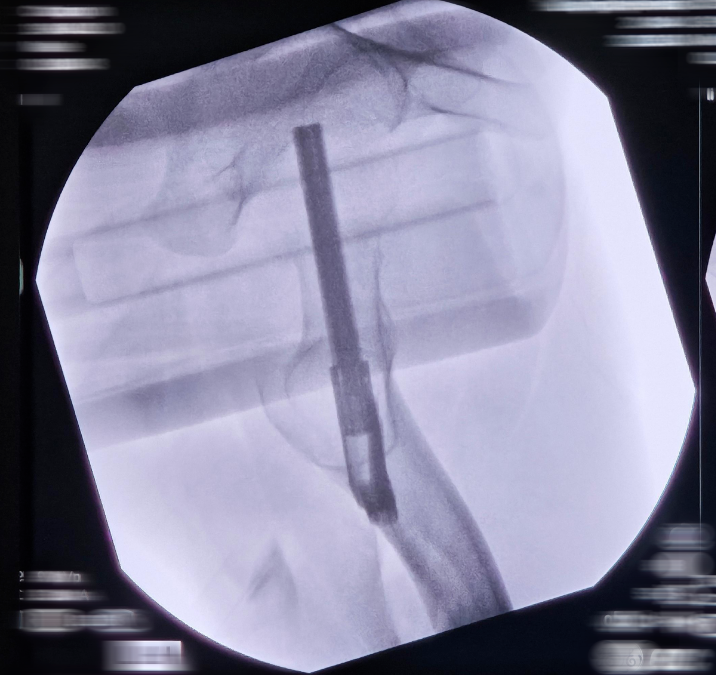

Surgical Technique Overview

1. Fracture reduction under imaging

2. Guidewire placement

3. Insertion of bolt and anti-rotation screw

4. Controlled compression fixation

image.pngimage.png